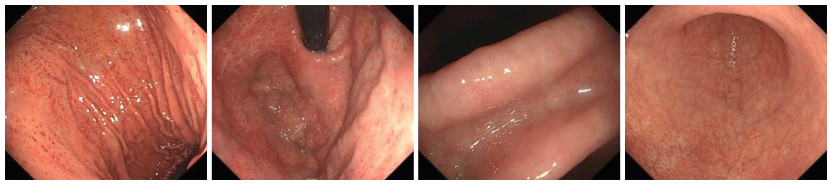

Research progress on the application of information-based medical care in monitoring patients with digestive tract tumors

LI Shuang, WANG Shixin, LI Yu, ZHAO Yanxin, LI Xinyu, WANG Yujie, REN Zhen

2025, 23(6): 1013-1017. doi: 10.16766/j.cnki.issn.1674-4152.004055

56 5

Abstract:

For a long time, the standardized diagnosis and treatment of gastrointestinal tumors have faced significant challenges. Limited understanding of tumor pathogenesis hampers the accuracy of early screening, while the lack of effective individualized treatment strategies for patients with advanced stages and the inability to accurately assess prognosis further complicate prevention, diagnosis, and treatment. However, the boom in information-based medical care has brought a breakthrough change to the current medical situation. This information-based medical model effectively utilizes intelligent data models to support clinical diagnosis and treatment for patients with gastrointestinal tumors, significantly enhancing the accuracy of tumor screening. Additionally, the integration of information-based medical care with intelligent auxiliary equipment enables home medication supervision and self-health management, providing a more comprehensive and accurate approach to patient condition monitoring. This paper analyzes the research status of information medicine in the monitoring of patients with digestive tract tumors, both domestically and internationally. It thoroughly discusses the advantages of information medicine model, examines its limitations and challenges, and evaluates the application of information medicine in the future. The aim is to provide a useful reference for improving the treatment and management mode of patients with digestive tract cancer, thereby advancing the overall level of the diagnosis and treatment, and fostering greater hope for better treatment effects to patients.